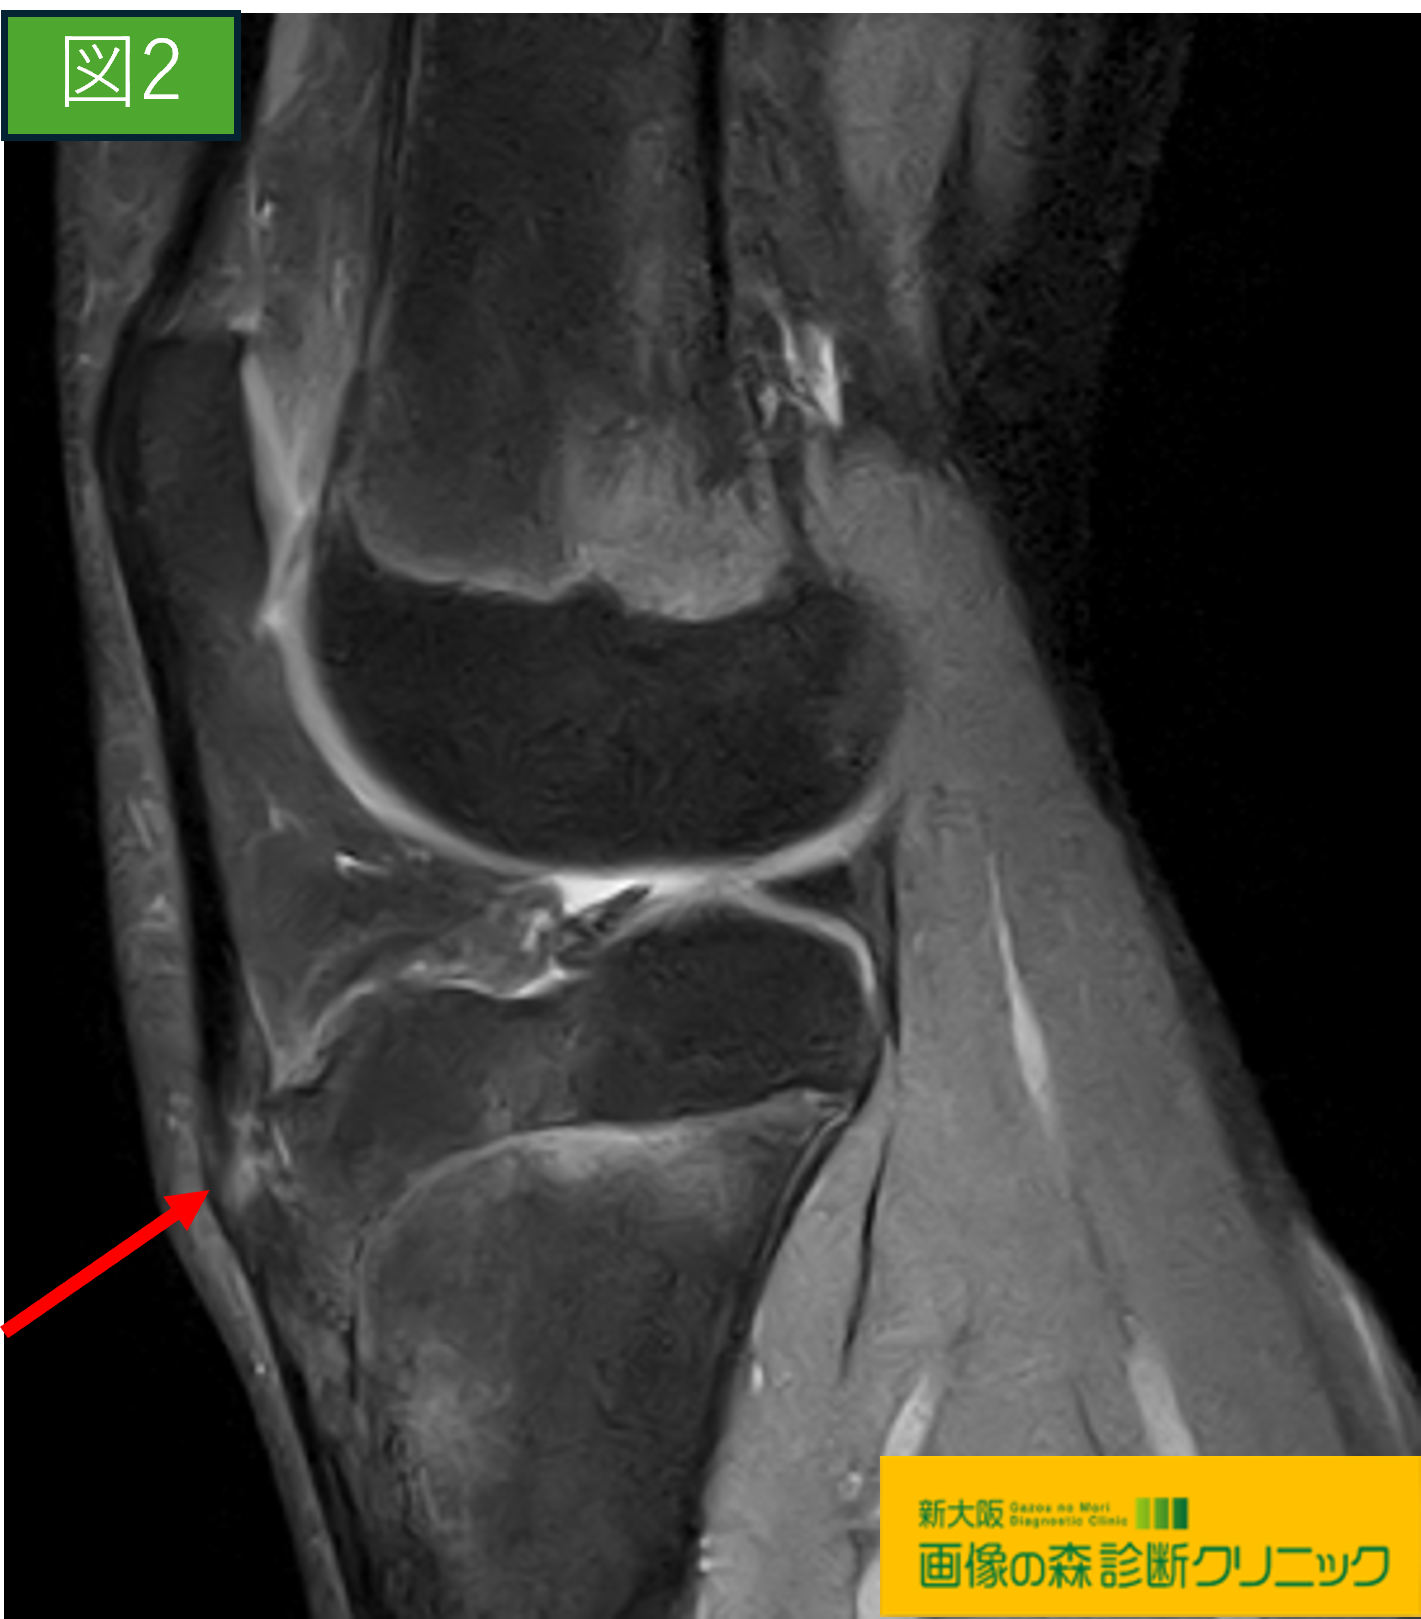

画像から図1・図3は正常膝関節の画像です。

図2・図4ではOsgood-Schlatter病の症例を示しています。

〇図1・図2の画像は膝関節部を横から見た画像であり、

それぞれの赤矢印にご注目下さい。

図1は正常画像

図2の症例画像では、赤矢印の黒い帯状の低信号帯に

白く高信号が見られます。

これは膝蓋靱帯の脛骨付着部の損傷を示しており、

脛骨粗面にも剥離が見られます。